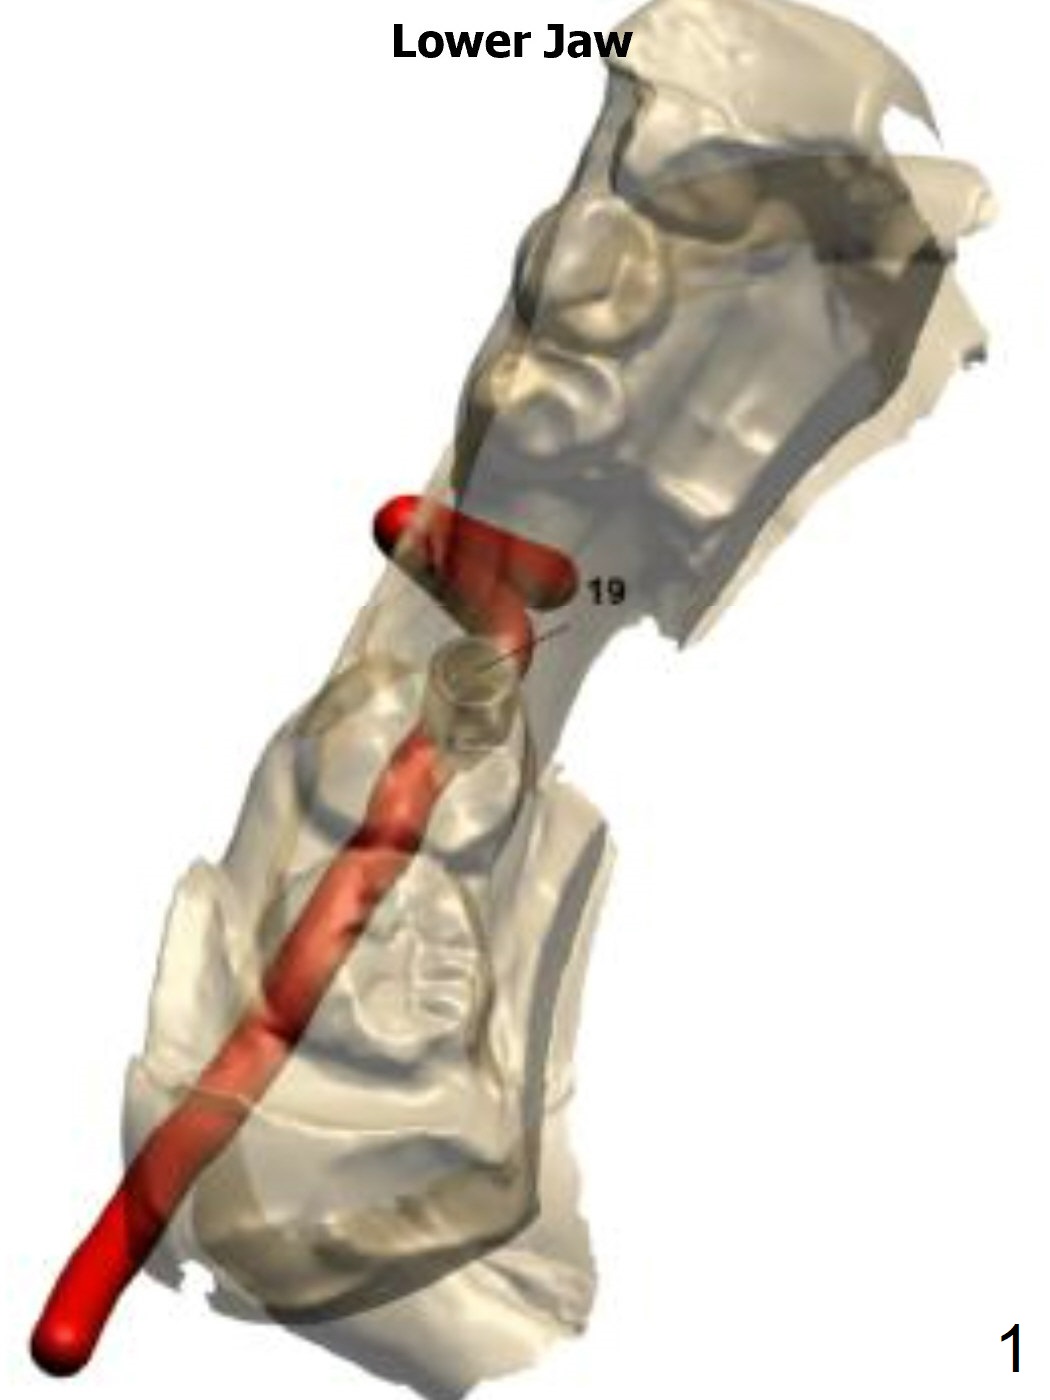

Guided surgery will be conducted at #19 post mini-implant placement for the opposing tooth intrusion.